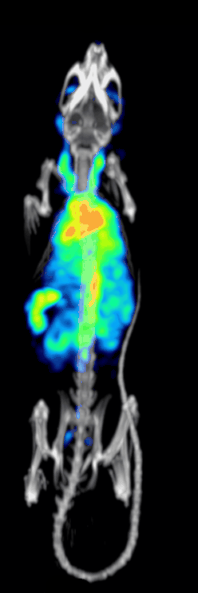

High resolution 99mTc-MDP mouse scan acquired with a stationary SPECT system: animated image of rotating maximum intensity projections.